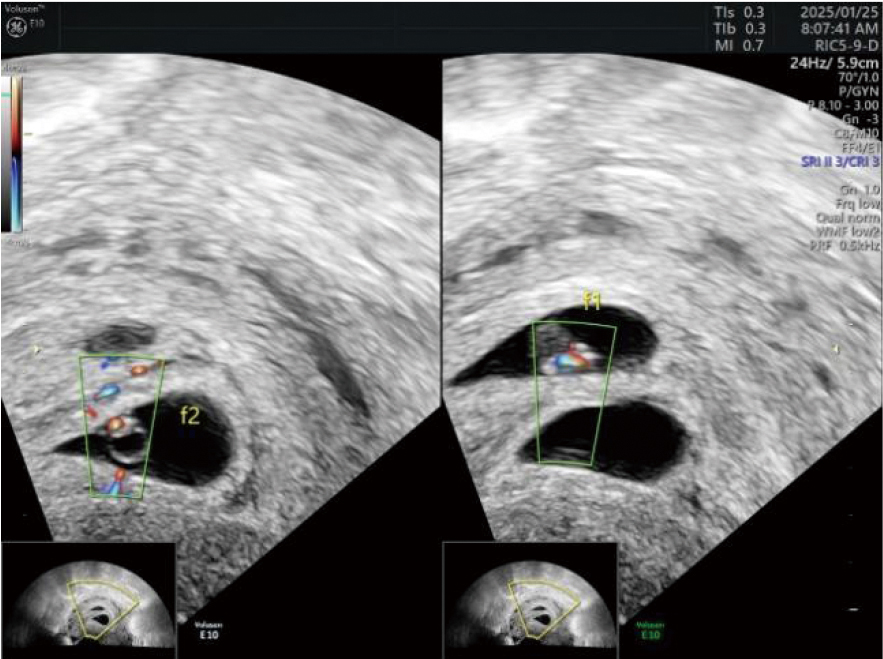

妊娠合并盆腔静脉丛血栓形成是一种较严重的妊娠并发症。该病发病率低,临床表现不典型,一般不易察觉。报告1例辅助生殖技术妊娠后,于孕40+ d常规彩色多普勒超声检查发现盆腔静脉丛内团块,超声提示早孕合并盆腔静脉丛血栓形成,后经给予低分子肝素抗凝和地屈孕酮保胎治疗后血栓消失,母婴预后良好。报道此病例旨在提高超声医师及临床医师对本病的认识,对临床化验及家族史可疑存在“易栓症”的孕妇,超声检查既要包括宫内胚胎发育情况、附件区情况,又要注意盆腔静脉丛的检查,对盆腔静脉丛血栓形成做到早期诊断和早期治疗,改善母胎结局。

Pelvic venous plexus thrombosis complicating pregnancy is a relatively severe pregnancy-related complication. This disease has a low incidence rate and atypical clinical manifestations, so it is generally difficult to detect. We report a case where, after pregnancy achieved through assisted reproductive technology, a mass in the pelvic venous plexus was detected by routine color Doppler ultrasound examination at more than 40 days of gestation. The ultrasound indicated early pregnancy complicated with pelvic venous plexus thrombosis. After anticoagulant treatment with low-molecular-weight heparin and tocolysis treatment with dydrogesterone, the thrombus disappeared, and the prognosis of the mother and the infant was good. The purpose of reporting this case is to improve the awareness of this disease among ultrasound physicians and clinical physicians. For pregnant women with suspected "thrombophilia" based on clinical laboratory tests and family history, the ultrasound examination should include the intrauterine embryonic development, the condition of the adnexa, and also pay attention to the examination of the pelvic venous plexus, so as to achieve early diagnosis and early treatment of pelvic venous plexus thrombosis and improve the maternal-fetal outcomes.